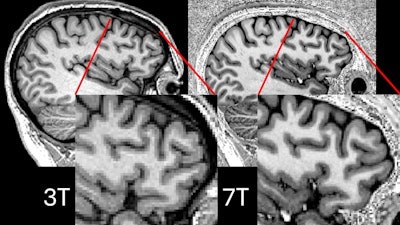

Comparison showing 3-tesla and 7-tesla scans for the same participant. Image courtesy of P Simon Jones, PhD, of the University of Cambridge.Comparison showing 3-tesla and 7-tesla scans for the same participant. Image courtesy of P Simon Jones, PhD, of the University of Cambridge.

Ultrahigh field 7-tesla MRI brain scans offer more detailed resolution and can help detect lesions in patients with drug-resistant epilepsy better than 3-tesla MRI devices, according to the group. But even though 7-tesla MRI has benefits over 3-tesla, it can still be limited by the signal dropouts. Klodowski and colleagues and a team from the Université Paris-Saclay in France tested the parallel transmit technique, which uses eight transmitters around the brain rather than just one to avoid these dropouts.